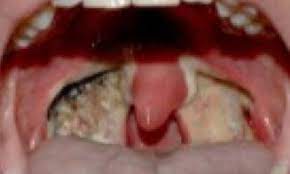

Tonsillectomy Wikipedia

Tonsillectomy Wikipedia from upload.wikimedia.org